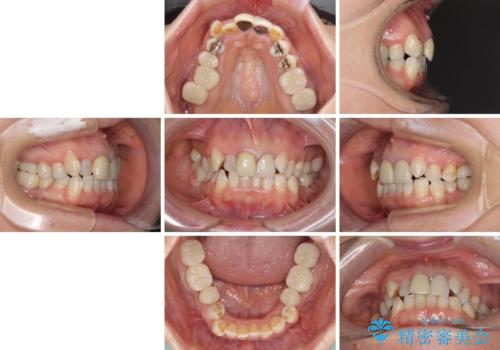

- 全顎的な歯列不正と、銀歯だらけの奥歯を気にして来院された患者様です。

奥歯の銀歯は、セラミッククラウンを装着するには歯の高さが不十分であり、そのままでは矯正治療を行うことが困難であるため、歯冠長延長術を行うこととしました。

また、根管治療の必要な歯がいくつかあるため、歯周外科治療の治癒期間を利用して根管治療を行い、その後インビザラインにて矯正治療を行うこととしました。

矯正治療後にはオールセラミッククラウンにて補綴治療を行うこととしました。

歯冠長延長術を行ったことで、自然な形態かつ清掃性の高いセラミッククラウンを装着することができました。

全顎的に治療を行ったため、治療期間も費用も負担は大きくなりましたが、統一感のある仕上がりとなりました。